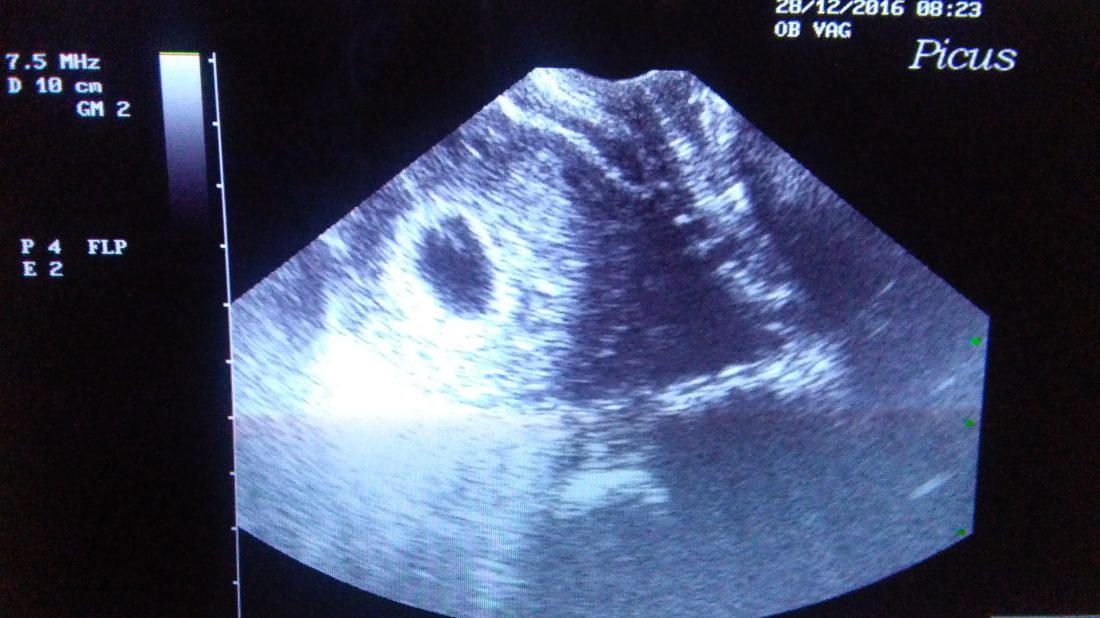

V nemocnici to pak už byla jen jízda. Jako bych šlápla na klouzačku a jela. Doktorka se mě ptala, jaký nález jsme našli u pana doktora a pak mi to jen potvrdila. Jelikož jde o fakultní nemocnici, po tom, co mi sdělila, že plodový vak je prázdný a dítě se tedy přestalo vyvíjet hned na začátku, to dalších 5 minut vysvětlovala studentce. Chápu to, kdyby tohle nebylo, neměli bychom doktory, ale mně se chtělo plakat a vlastně jsem za celou dobu nedostala příležitost. Slezla jsem z kozy a doktorka začala vypisovat zprávu s tím, že kdybych byla na lačno, tak by mě vzali hned dneska, abych nemusela čekat a trápit se doma. Jelikož jsem na lačno byla, kromě pár loků té coly, tak mě hned přijali. Vlastně, musel jsem jít na chodbu chvilku počkat, aby se domluvila s anesteziologem, jestli to půjde. Šlo to.